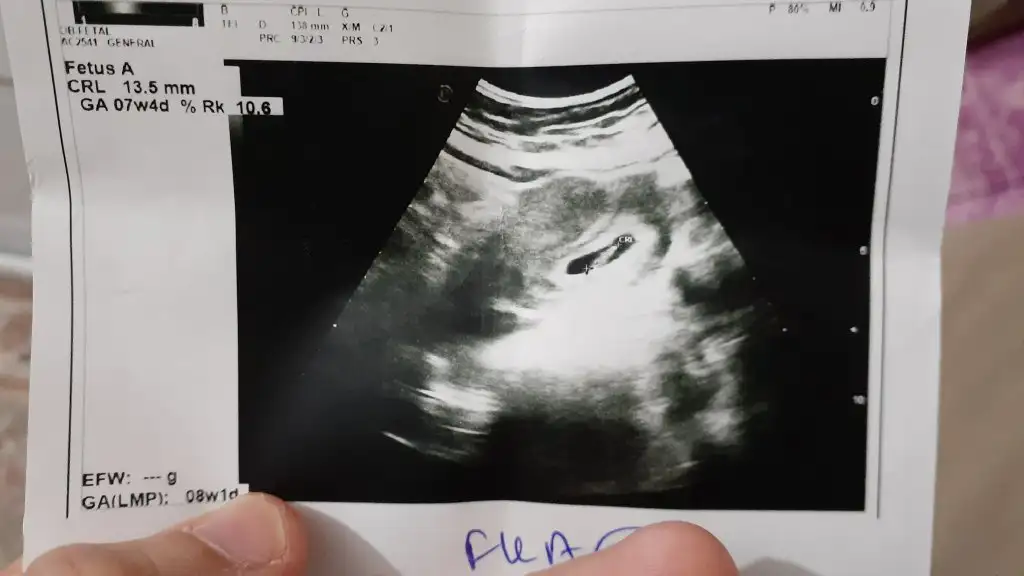

Bende kız hissediyorum bakalım ne çıkacakKız buna göre tabiki en iyi 11 12 13 haftalar olmalı

Kese için büyük nub için küçük 11 12 13 haftalar olmalı9 haftalık resim ikra meyra yorumlayabilirmisiniz cinsiyetini:)

Ama haftasında önemli 6+hafta olmalıBende kız hissediyorum bakalım ne çıkacak